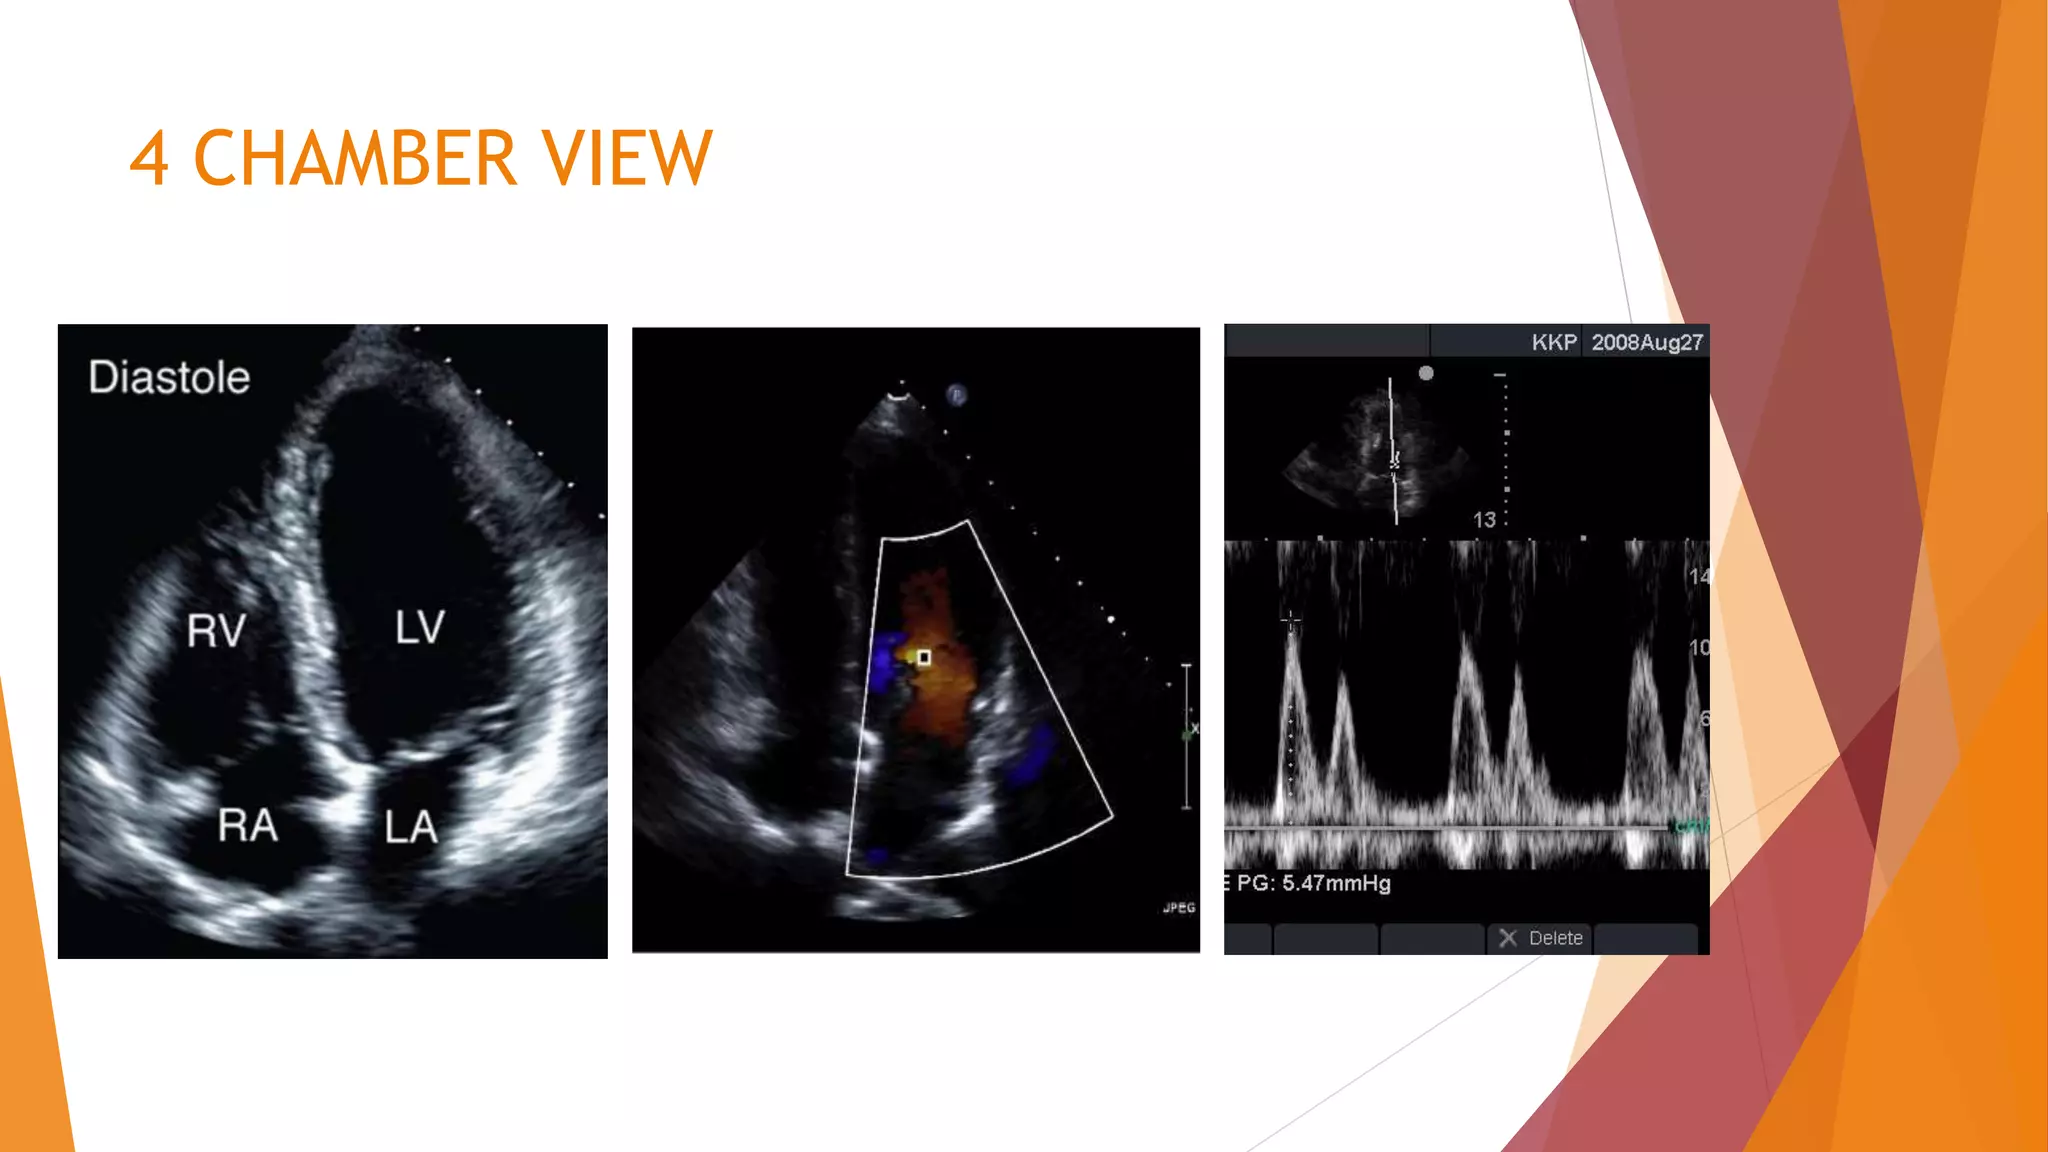

This document discusses using echocardiography to diagnose and manage acute respiratory failure. It outlines how echocardiography can differentiate between cardiogenic pulmonary edema caused by left heart failure and non-cardiogenic pulmonary edema caused by conditions like acute respiratory distress syndrome. It provides guidance on using echocardiography to estimate left ventricular filling pressures and diagnose diastolic heart failure. It also explores how echocardiography can evaluate right ventricular function in patients with acute respiratory failure and pulmonary edema.